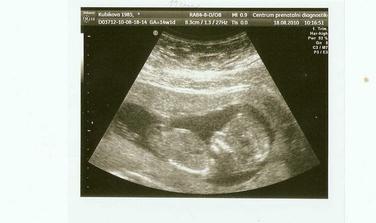

18.8. jsme absolvovali NT+ screening v Brně a výsledek je na jedničku, máme 11cm a vše tam jak má být...moc jsme si oddechli...a víme i pohlaví, ale zatím si to necháváme s manžou pro sebe 🙂